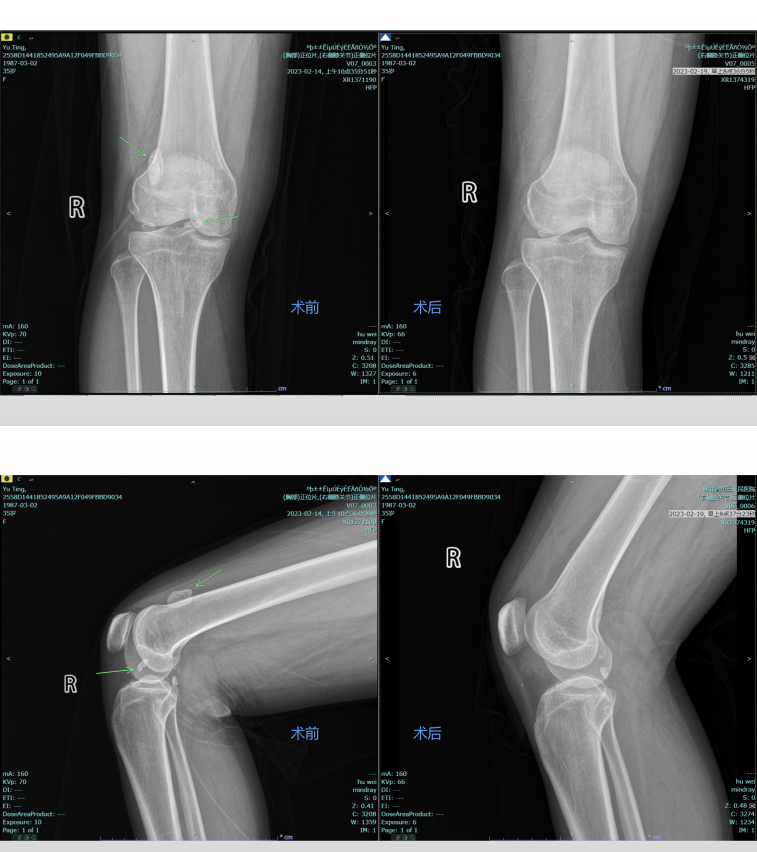

术前及术后对比

面对手术治疗,余女士心怀顾虑,对即将到来的手术有些许不安与畏惧。“这个问题好解决吗?”余女士很是忐忑,王显勋介绍,现在都是利用关节镜微创手术取出游离体,“关节镜微创手术不需要切开膝关节,只需要在膝盖下切两个0.5厘米的切口,插入关节镜和操作钳,就能在镜下完成所有的操作,创伤小,恢复也快。”

术后第二天,余女士被告知可以下地活动,“做了手术不是应该在床上躺着吗?这么快就下地真的没问题吗?”余女士满脸疑惑。“放心吧,现在不同以往了,微创手术旨在尽量小的创口下解决患者的问题,创口小了,术后恢复自然就快,所以就能早期下床活动”。王显勋解释到,“你再试试弯一下膝盖,看看还有没有卡住的感觉”。在管床医生的帮助下,余女士缓缓屈伸膝关节,发现之前困扰自己的症状已经不复存在了,在之后的膝关节锻炼中,也没有再出现“卡住”的感觉,这终于让余女士放下了心。最终,在医护的悉心照料下,术后第五天,余女士恢复良好,顺利出院。